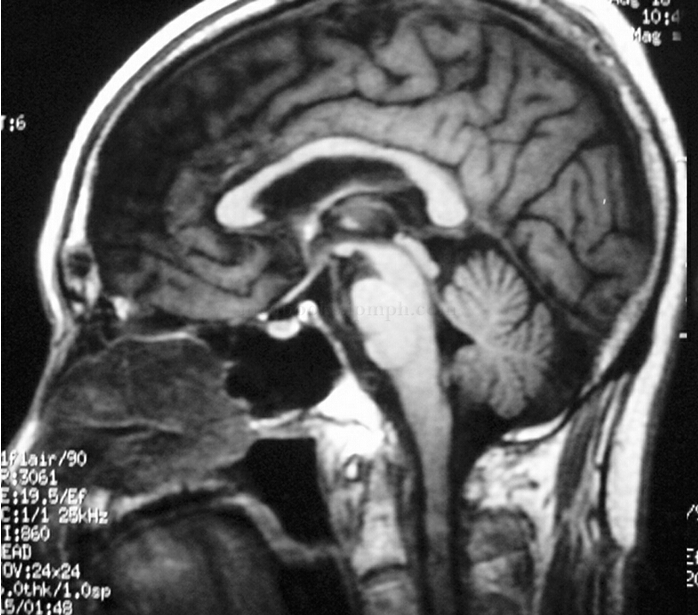

1小时条评论男,79岁,右利手。 主诉:眩晕2天。 病史:入院前2天无诱因突然出现持续头晕、视物旋转,伴耳鸣、耳闷,偶尔恶心,无呕吐,症状于活动时加重,休息时好转。查体:卧位血压168/105mmHg,坐位112/65mmHg,高级神经系统检查正常,脑神经(-),面部表情欠丰富,四肢...